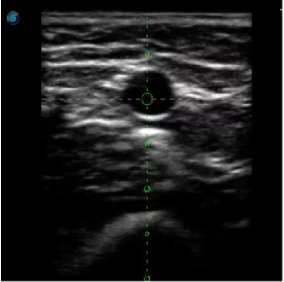

傳統(tǒng)腔內(nèi)探頭采用直柄設(shè)計,在搭配穿刺架使用時,手術(shù)空間小,不易操作;生殖專用的曲柄探頭,探頭柄采用彎曲成角度設(shè)計,可實現(xiàn)監(jiān)視、取卵兩不誤,搭載穿刺架時,可以清晰顯示穿刺針的進針過程、深度和位置,實時監(jiān)視取卵全過程,保障取卵操作精準(zhǔn)與安全。

取卵臨床圖